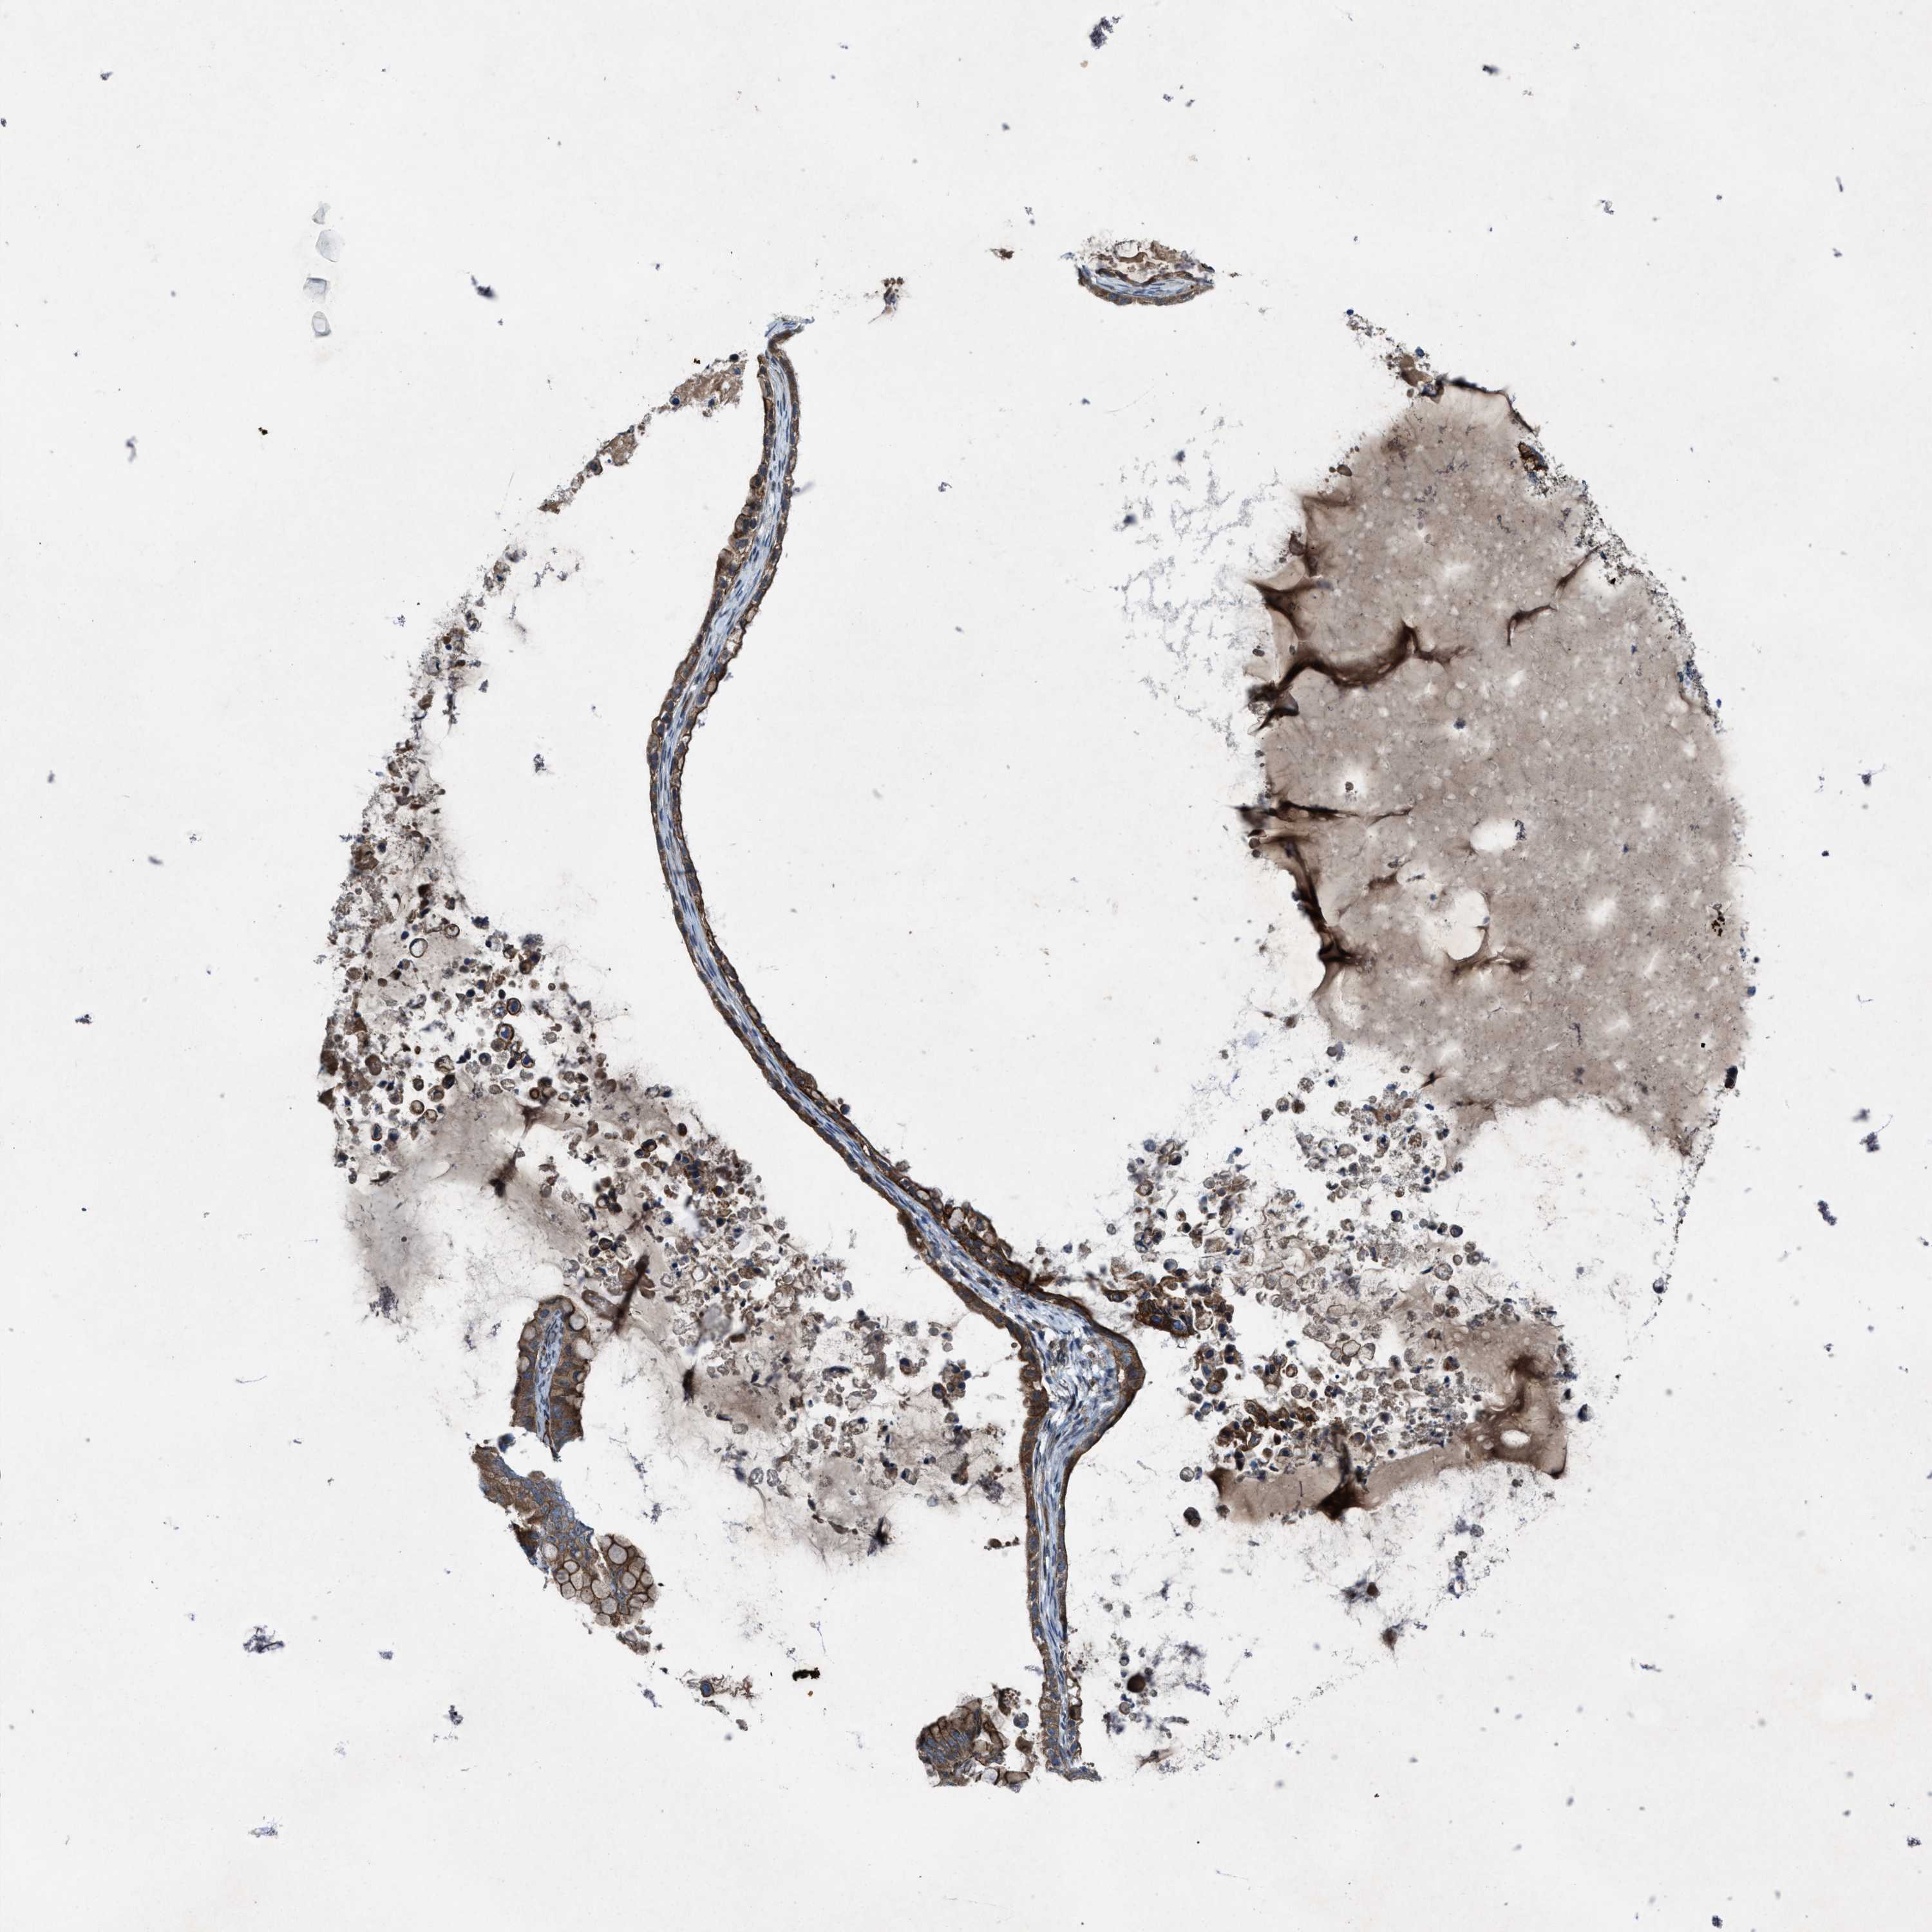

OVARIAN CANCER - Protein expressioni

A mouse-over function shows sample information and annotation data. Click on an image to view it in a full screen mode. Samples can be filtered based on level of antibody staining by selecting one or several of the following categories: high, medium, low and not detected. The assay and annotation is described here.

Note that samples used for immunohistochemistry by the Human Protein Atlas do not correspond to samples in the TCGA dataset.

Antibody stainingi

Antibody staining in the annotated cell types in the current human tissue is reported as not detected, low, medium, or high, based on conventional immunohistochemistry profiling in selected tissues. This score is based on the combination of the staining intensity and fraction of stained cells.

Each image is clickable and will lead to virtual microscopy that enables deeper exploration of all samples and also displays staining intensity scores, fraction scores and subcellular localization as well as patient and tissue information for each sample.

Antibody HPA019879

Antibody HPA020134

Antibody HPA029468

Cystadenocarcinoma, serous, NOS

Carcinoma, endometroid

Cystadenocarcinoma, mucinous, NOS

Carcinoma, NOS